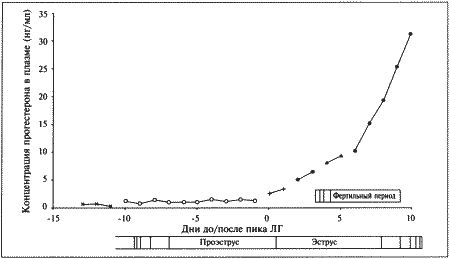

Фиг. 1.2.

Динамика концентрации прогестерона в плазме крови на протяжении эстрального цикла. Составлено на основании данных, полученных при наблюдении за 8 собаками. За точку отсчета принят овуляторный пик ЛГ. Ключевые показатели, используемые для идентификации стадии цикла и вычисления фертильного периода (см. текст): концентрация прогестерона в конце анэструса находится на базальном уровне (может не выявляться) (х-х), затем в период проэструса незначительно повышается до определяемого уровня (о-о); в период, предшествующий овуляции, концентрация прогестерона возрастает одновременно с пиком ЛГ (+-+). За временной интервал между пиком ЛГ (▲-▲) и овуляцией уровень прогестерона повышается до характерных значений начала фертильного периода и продолжает увеличиваться (-•) приблизительно до 30 дня.

Предполагаемый фертильный период — от 4-го до 7-го дня.

Примечания:

— кровянистые выделения появляются за несколько дней до начала эструса;

— самка подпускает к себе самца непосредственно перед началом фертильного периода;

— последний день восприимчивости может наблюдаться спустя несколько дней после окончания фертильного периода, т. е. в начале метэструса;

— начало уменьшения отека слизистой оболочки обычно наблюдается перед пиком ЛГ.

Данные о концентрации прогестерона в сыворотке крови могут служить ориентиром для определения фертильного периода у сук. Механизмы и динамика изменения концентрации прогестерона описаны в предыдущем разделе (фиг. 1.2).

В конце анэструса концентрация прогестерона в сыворотке крови находится на базальном уровне (и практически не определяется), к окончанию проэструса она повышается до низкой, но поддающейся определению отметки (около 3 нмоль/л или 1 нг/мл). И продолжает повышаться, достигая уровня 3–6 нмоль/л (1–2 нг/мл) к моменту овуляторного пика ЛГ; 2 дня спустя (в день овуляции) показатели достигают 6–12 нмоль/л (2–4 нг/мл), а к 4 дню (т. е. к началу фертильного периода) — 18–30 нмоль/л (6–10 нг/мл) (фиг. 1.1). Концентрацию прогестерона определяют в плазме крови, поскольку анализ других жидкостей (слюны и мочи) в настоящее время не дает точных результатов. Исследование проводят после появления первых признаков проэструса и повторяют по меньшей мере каждые 2–3 дня до окончания проэструса или начала поведенческого эструса. Такая методика позволяет выявлять стремительное нарастание концентрации прогестерона перед овуляцией и соответственно рассчитать дату возможной вязки. В случаях очень короткого проэструса исследование начинают раньше.